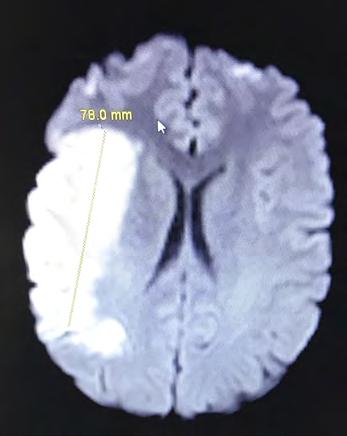

All of the positive things Amy has done for others certainly came back to her a thousand-fold when it was she who needed care and encouragement after suffering a major stroke following surgery. “When I was not waking up following surgery, the nurses called the vascular neurologist who evaluated me and felt that I was having a stroke,” Amy explained. “Fortunately, Wadley has 24/7 MRI coverage and CT perfusion abilities. I was taken for an MRI which revealed a large stroke and a blocked right middle cerebral artery, which basically supplies the part of the brain responsible for most of the movement and feeling sensations on the left side of the body.”

One of the initial images from Amy’s stroke taken in March 2017. It shows a very large right middle cerebral artery infarct.